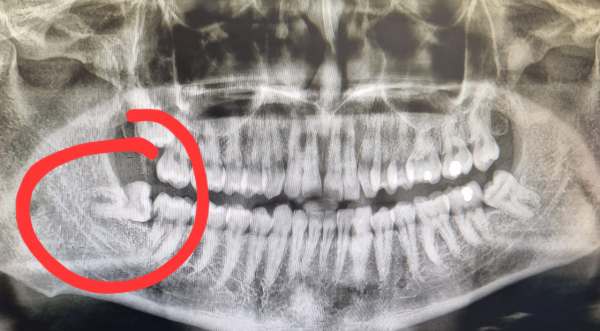

特に、横向きに生えている親知らずはトラブルにつながりやすく、抜歯を検討することが多いです。横向きに生えると隣の歯を圧迫したり、歯ぐきに埋まったまま炎症を起こしたりすることがあるためです。

親知らずは一番奥に生えてくるため、他の歯が並んでいる状態でスペースが確保できない場合があります。そのため、横向きや斜めに生える、または埋まったままになることが多いのです。この状態を埋伏(まいふく)歯といいます。

完全に歯ぐきの中に埋もれているケースも珍しくありません。この場合、別の治療などでレントゲンを撮影した際に発見されることが多いです。

まず、歯科医院で診察を受け、レントゲンやCTスキャンを撮影します。親知らずの正確な位置、神経や血管との距離、歯の埋まり具合などを確認します。特に、下顎の親知らずは神経が近くにあるため、慎重な診断が必要です。